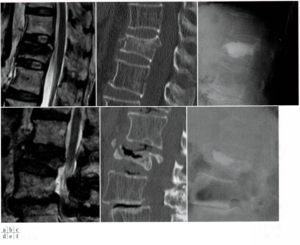

図3 椎体骨折受傷後、1か月(上段)、6か月(下段)の比較

a(左上):L1椎体骨折受傷後1か月でのMRI T2強調像で広範囲型低信号を認める。

b(中上):CTで同部位に後壁損傷を認める。

c(右上):BKP後の単純X線画像

d(左下):L2椎体骨折受傷後6か月のMRI T2強調画像で椎体内低信号を認める。

e(中下):後壁を含む骨折椎体の圧潰が著明であり,終板の一部欠損を認める。

f(右下):BKP後の単純X線画像

これらを踏まえて改めて図3(a.d)を見てみると…

a:L1椎体骨折受傷後1か月でのMRI T2強調像で広範囲型低信号を認める。

⇒L1の広範囲が圧潰/骨硬化している=骨構造が破綻した範囲が広く不安定であり、BKP適応寄りの所見と言える。

d:L2椎体骨折受傷後6か月のMRI T2強調画像で椎体内低信号を認める。

⇒圧潰、eのCT画像からも低信号は椎体内クレフトであると言える。